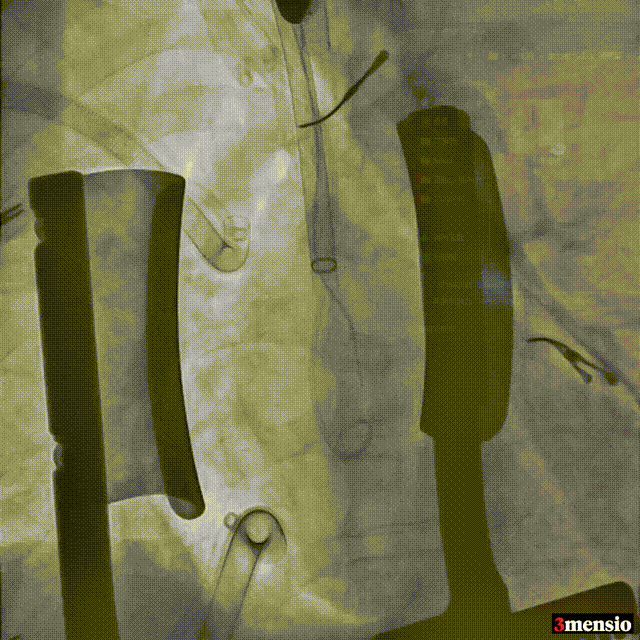

瓣膜释放后超声情况:

短轴超声

长轴超声

术后压差 5mmHg

术后患者情况

在心血管内科吴连拼教授带领心脏瓣膜团队成功完成经升主动脉途径TAVR后,再由赵琦峰教授带领心胸外科团队先后对患者的右冠、前降支、回旋支行冠脉搭桥术。术后复查显示主动脉到前降支静脉桥以及主动脉至对角支、第一钝缘支、左室后支序贯桥通畅;心电图示窦性心律,未见心肌缺血表现。